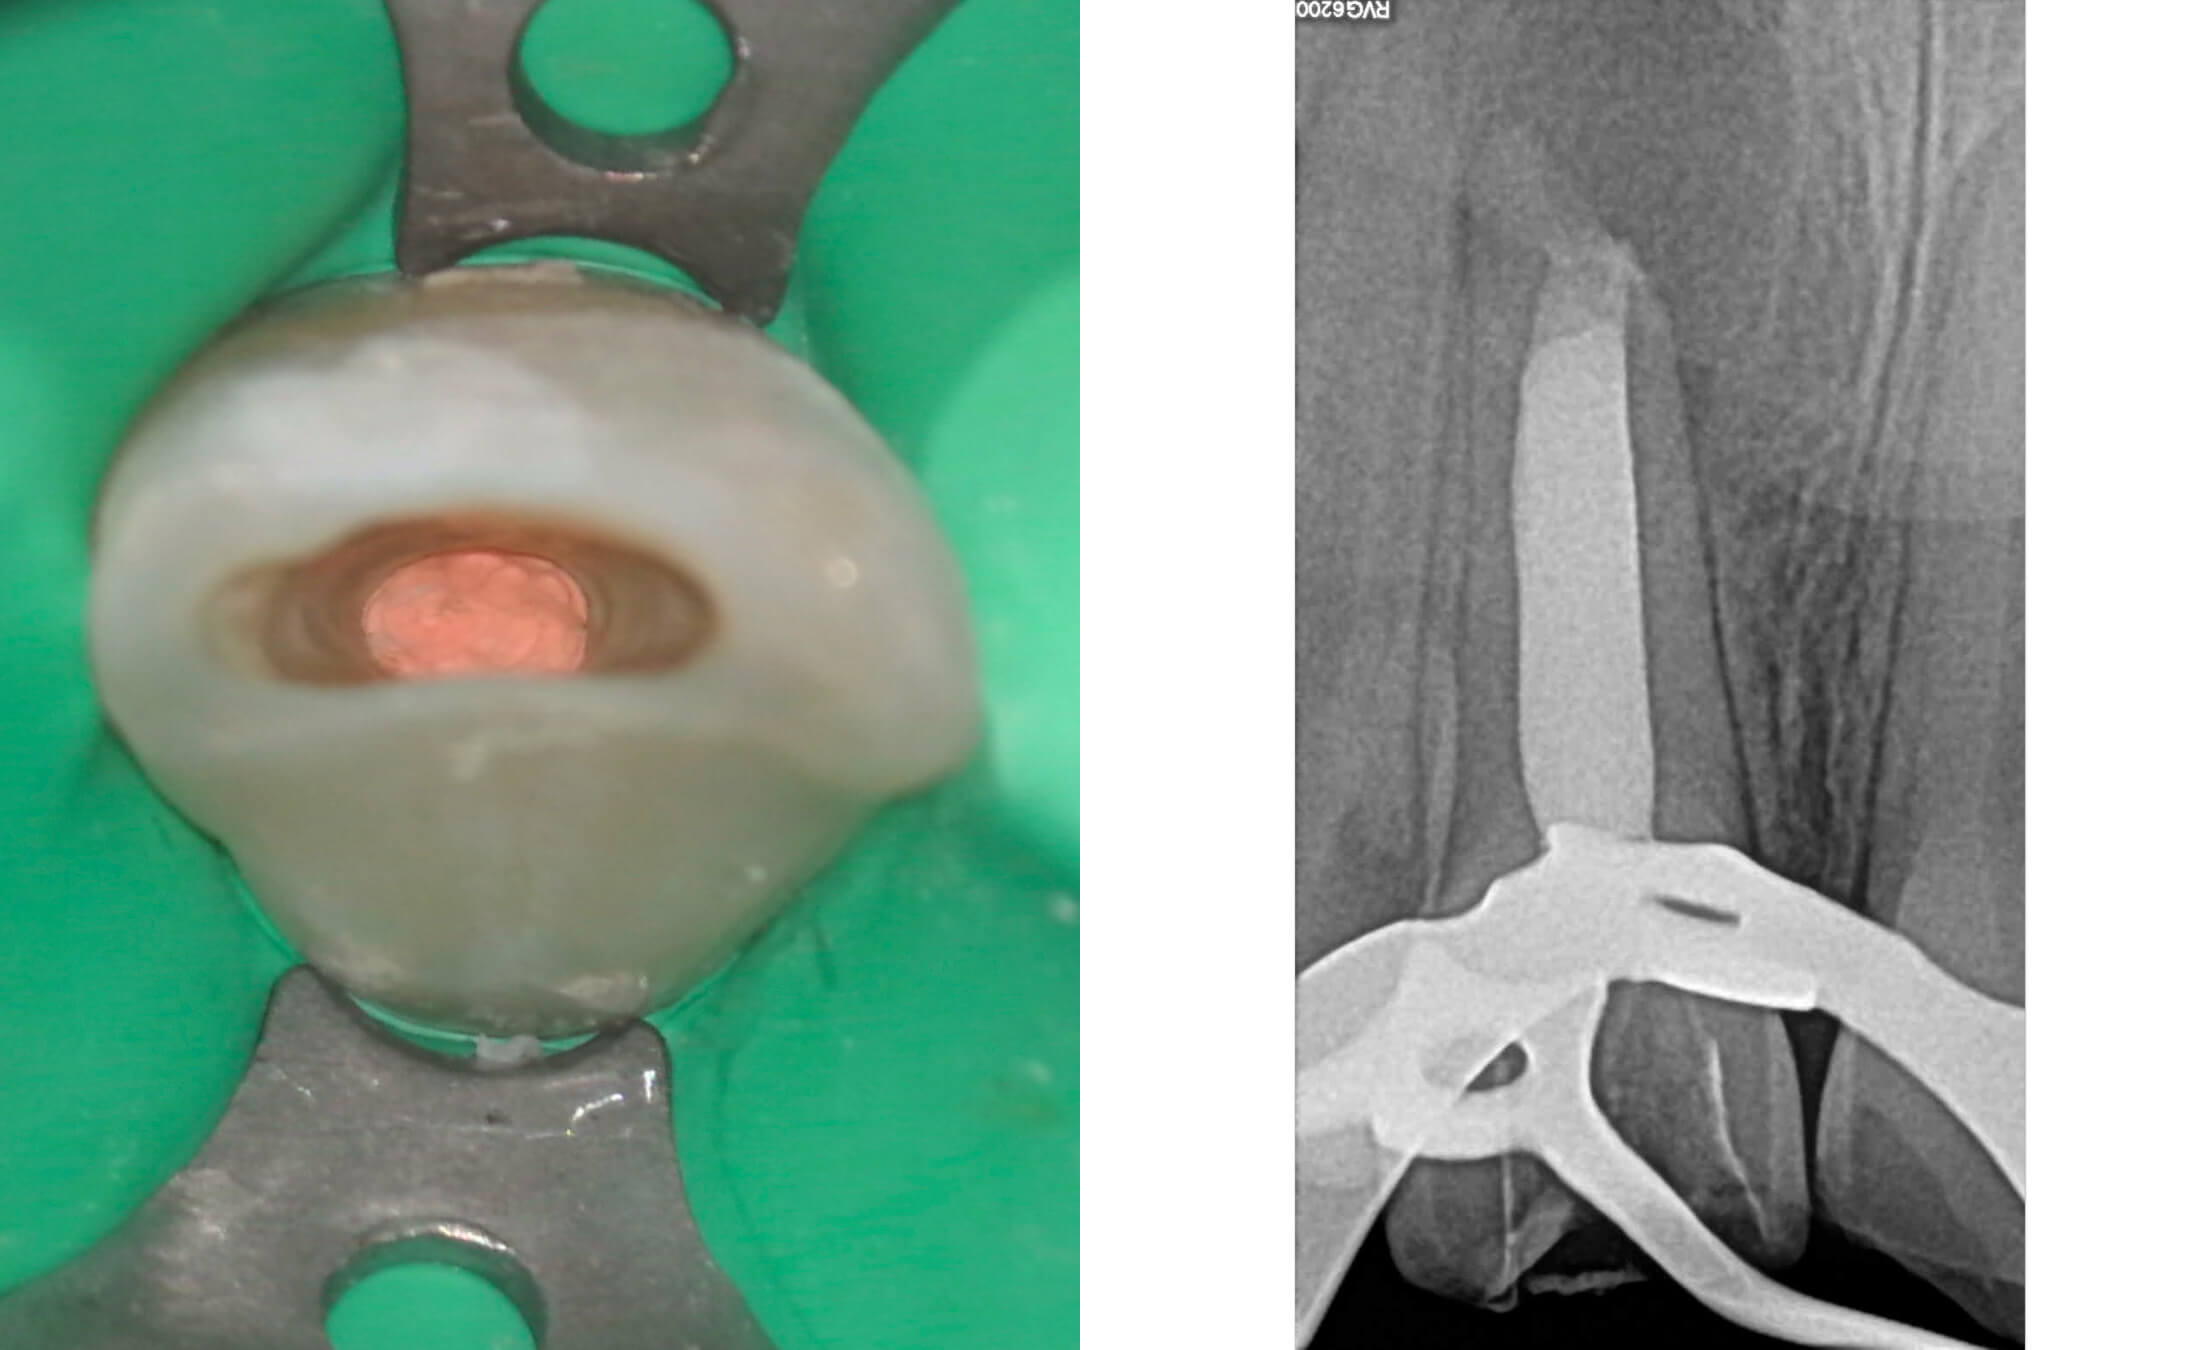

1. Ребенок, перенес травму зубов около 5 лет назад, стоматологическая помощь не была оказана своевременно. (Фото 1)

2. Зуб 11 девитален, апикальный периодонтит с обширной деструкцией костной ткани, зуб 12 витален. (Фото 2,3,4)